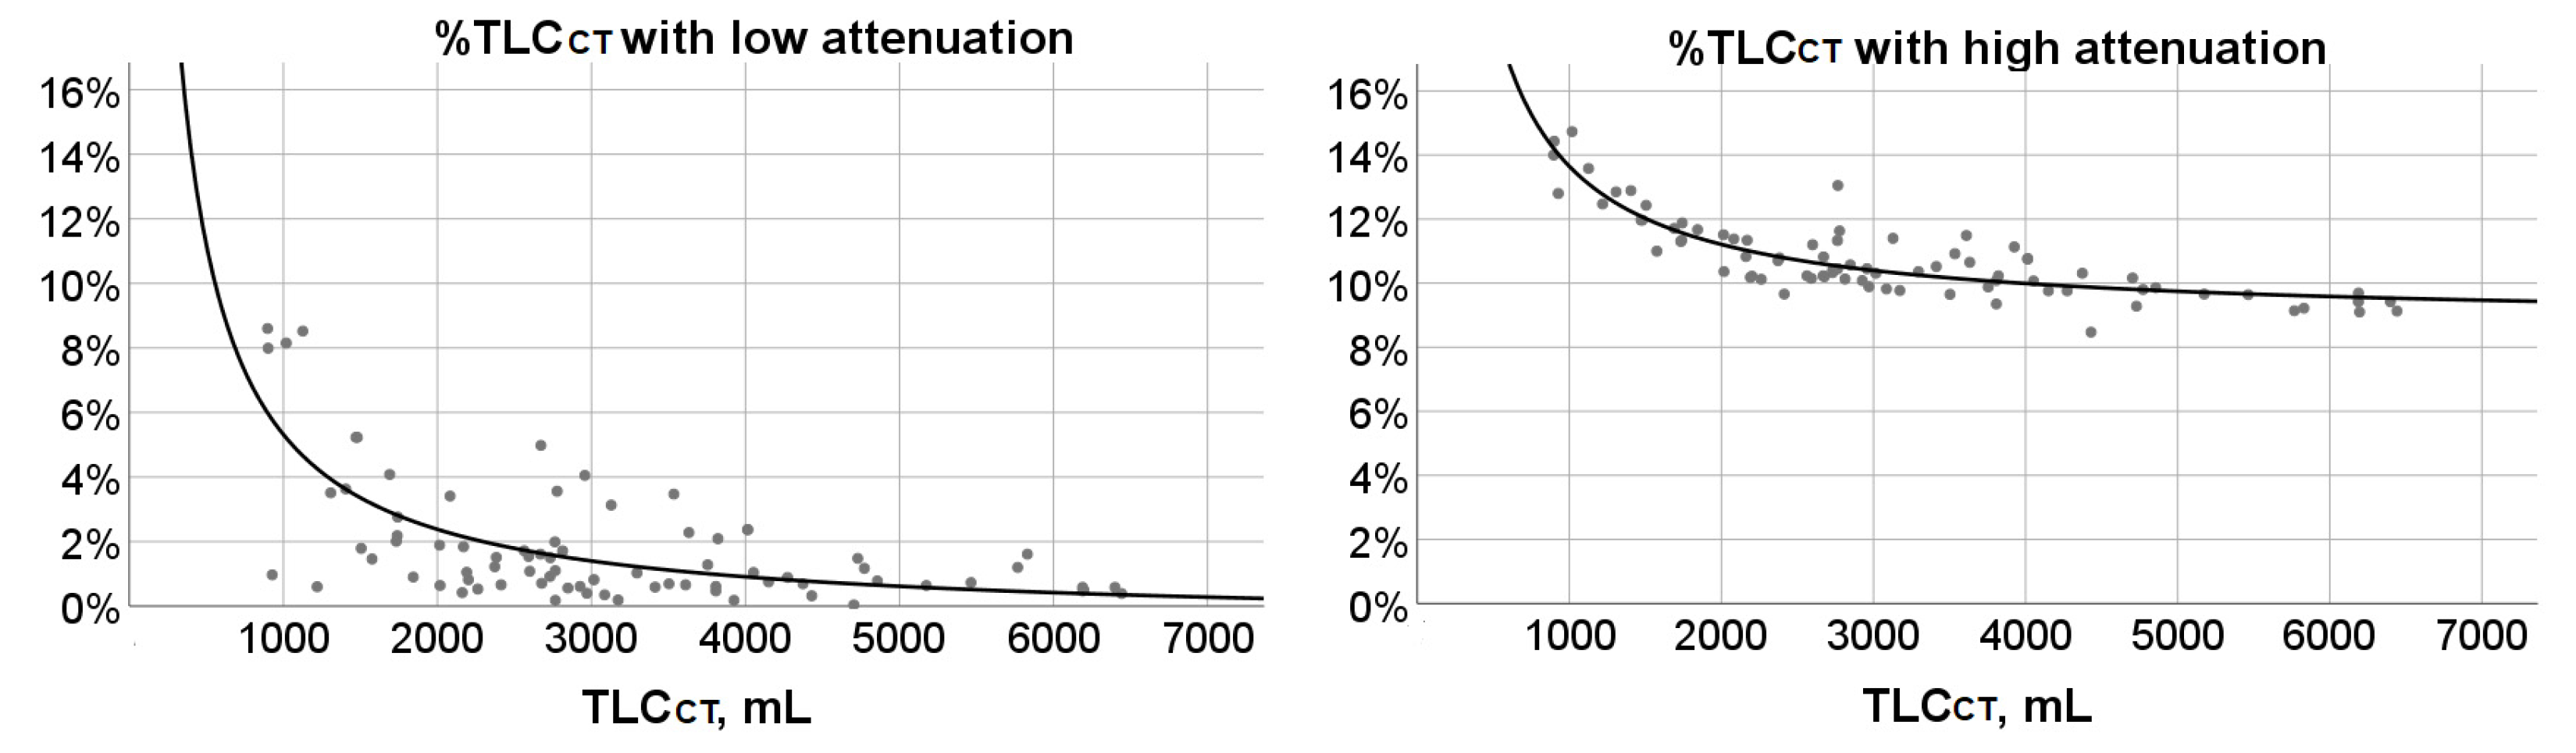

3.4. %TLCCT with Low or High Attenuation and Their Associations with Age and TLCCT

| Age Group | %TLCCT with Attenuation < Low Attenuation Threshold | %TLCCT with Attenuation > High Attenuation Threshold | TLCCT, mL | %TLCCT with Attenuation < Low Attenuation Threshold | %TLCCT with Attenuation > High Attenuation Threshold |

|---|---|---|---|---|---|

| 6-year-old (n = 7) | 1.46 (0.90, 7.99) (0.60, 8.60) | 12.47 (11.33, 14) (11, 14.43) | 897.3–1500 (n = 10) | 5.23 (2.88, 8.24) (0.60, 8.60) | 12.87 (12.35, 14.11) (11.97, 14.73) |

| 7-year-old (n = 6) | 2.85 (1.02, 5.96) (0.82, 8.15) | 11.66 (10.96, 13.32) (10.22, 14.73) | 1501–2000 (n = 7) | 2.01 (1.46, 2.76) (0.90, 4.08) | 11.67 (11.30, 11.88) (11.00, 12.43) |

| 8-year-old (n = 7) | 3.63 (1.22, 5.23) (0.19, 8.52) | 11.71 (10.70, 12.89) (9.77, 13.58) | 2001–2500 (n = 11) | 1.05 (0.64, 1.84) (0.42, 3.41) | 10.70 (10.18, 11.34) (9.66, 11.51) |

| 9-year-old (n = 7) | 1.51 (0.64, 1.84) (0.18, 3.41) | 11.34 (10.36, 12.43) (10.31, 13.05) | 2501–3000 (n = 17) | 1.50 (0.66, 1.86) (0.18, 4.98) | 10.43 (10.18, 11.01) (9.89, 13.05) |

| 10-year-old (n = 7) | 0.53 (0.40, 1.05) (0.18, 1.89) | 10.20 (10.12, 11.13) (9.89, 11.51) | 3001–3500 (n = 6) | 0.71(0.31, 1.56) (0.19, 3.13) | 10.34 (9.81, 10.74) (9.77, 11.40) |

| 11-year-old (n = 7) | 0.92 (0.56, 2.76) (0.35, 4.98) | 10.52 (10.13, 10.82) (9.82, 11.88) | 3501–4000 (n = 9) | 0.69 (0.54, 2.19) (0.18, 3.47) | 10.23 (9.77, 11.03) (9.35, 11.49) |

| 12-year-old (n = 6) | 1.45 (0.96, 3.49) (0.73, 3.56) | 10.30 (9.82, 11.10) (9.64, 11.63) | 4001–4500 (n = 7) | 0.89 (0.69, 2.37) (0.32, 2.37) | 10.07 (9.76, 10.76) (8.47, 10.76) |

| 13-year-old (n = 7) | 1.5 (0.89, 2.09) (0.66, 2.28) | 10.15 (9.66, 10.43) (9.28, 10.65) | 4501–5000 (n = 4) | 0.98 (0.23, 1.40) (0.04, 1.48) | 9.83 (9.41, 10.09) (9.28, 10.16) |

| 14-year-old (n = 6) | 0.77 (0.49, 1.06) (0.04, 1.10) | 9.97 (9.74, 10.23) (9.66, 10.45) | 5001–5500 (n = 2) | 0.69 (0.64, 0.73) | 9.65 (9.64, 9.66) |

| 15-year-old (n = 8) | 0.69 (0.48, 1.51) (0.47, 4.10) | 9.50 (9.16, 10.16) (9.10, 10.45) | 5501–6000 (n = 2) | 1.41 (1.20, 1.61) | 9.18 (9.14, 9.22) |

| 16-year-old (n = 6) | 1.17 (0.58, 2.37) (0.58, 2.37) | 10.23 (9.42, 10.76) (9.42, 10.76) | 6001–6500 (n = 5) | 0.50 (0.43, 0.58) (0.39, 0.58) | 9.42 (9.12, 9.56) (9.10, 9.69) |

| 17-year-old (n = 6) | 0.64 (0.37, 1.66) (0.32, 3.13) | 9.94 (8.97, 11.42) (8.47, 11.49) |